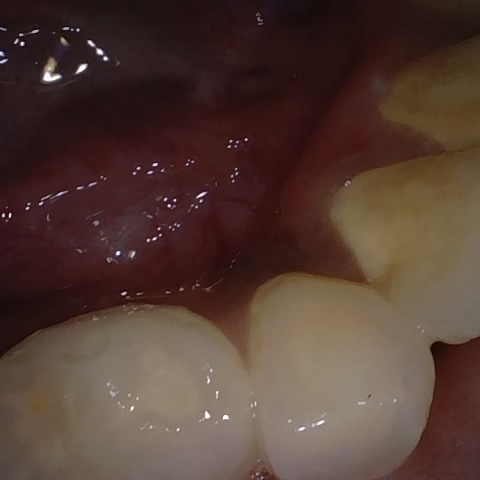

Annotated as "Good"